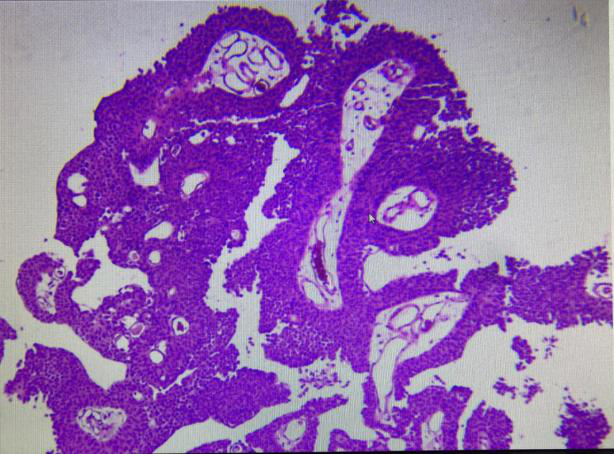

尿路上皮乳頭狀瘤占膀胱腫瘤的1%或更少。多見(jiàn)于青年。腫瘤呈乳頭狀,細(xì)胞分化好。